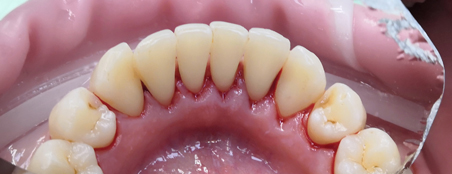

Наши работы

пародонтологов в КосмоСтом

Методы лечения зависят от того, насколько запущена болезнь. Вовремя замеченный гингивит лечится сравнительно легко. Пациенту подбирают подходящие средства для ухода за зубами и деснами, объясняют, как правильно ими пользоваться. Врач проводит аппаратную чистку зубов с помощью ультразвукового комплекса «Сателек», произведенного во Франции. Многочисленные насадки избавят зубы от налета совершенно безболезненно благодаря высокой квалификации специалистов клиники. При необходимости, пациентам с низким болевым порогом, будет проведена анестезия. После чистки пародонтолог даст рекомендации по уходу за деснами и зубами.

На ранней стадии пародонтита больному предстоит пройти те же процедуры чистки и борьбы с бактериями. В этом случае так же необходимо применение аппарата для снятия налета, неглубокие зубодесневые карманы промывают сильнодействующими растворами. Обычно болезнь отступает быстро, и, при условии надлежащей гигиены полости рта и регулярного наблюдения у пародонтолога, больше не возвращается.

Лечение десен ультразвуком на аппарате «Вектор»

Немецкая система «Вектор» – самый прогрессивный аппарат, применяющийся для лечения заболеваний десен. Перед началом сеанса врач проводит тщательную предварительную обработку зубов и десен. Специальными профессиональными пастами он удаляет мягкий налет на зубах, затем с помощью инструментов – твердые зубные отложения. Освобожденные поверхности сглаживаются, затем десны орошаются антимикробными растворами.

Подготовив больного, врач подключает ультразвуковой аппарат. В процессе лечения ультразвук через наконечник воздействует не на сам зуб, а на окружающую его жидкость, благодаря чему исключается вибрация, которая многих раздражает. Анестезии при таком методе не требуется: пациент не испытывает не только боли, но и просто неприятных ощущений. С помощью «Вектора» удаляются все отложения, даже в труднодоступных поддесневыхучастках, уничтожаются опасные микробы и продукты их жизнедеятельности, промываются карманы и полируются корни.

Твердые ткани зуба во время лечения остаются в полной безопасности, поскольку наконечник к ним не прикасается. Кроме того, в полирующем растворе содержатся частицы гидроксиапатита – минерала, использующегося в стоматологии для укрепления зубной эмали. Ультразвуковое лечение десен в Омске не травмирует десну, она не болит ни во время процедуры, занимающей в среднем около часа, ни по возвращении пациента домой.